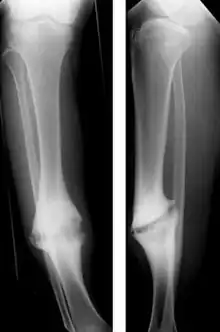

Pseudoartrose (grego antigo para falsa articulação) é uma séria complicação de uma fratura óssea na qual o osso nunca se regenera. Uma cicatriz de tecido fibroso se forma no meio do osso. Sem tratamento resulta em deformidade e prejuízo permanente da função, como por exemplo uma perna torta e incapaz de suportar peso se a pseudoartrose é no fêmur ou na tíbia. O tratamento é cirúrgico e a recuperação demora muitos meses.

O diagnóstico geralmente é feito nas consultas de seguimento seis a oito semanas depois da fratura com raio X e exame físico. Dor, fragilidade e incapacidade funcional indicam que o osso não se consolidou bem.[2] Em caso de dúvida a consolidação inadequada é melhor vista com tomografia computadorizada ou com radiografia dos movimentos disfuncionais (stress Rx).